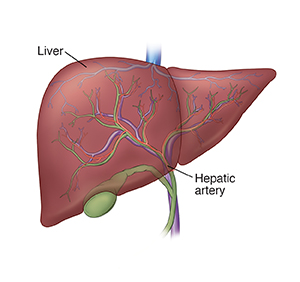

Chemoembolization is a way to treat cancer in the liver. It can be used for cancer that starts in the liver. Or it can be used for cancer that has spread (metastasized) to the liver from other parts of the body. The procedure treats cancer only in the liver. It is done by a specially trained health care provider (interventional radiologist).

The hepatic artery is a large blood vessel. It sends blood to the liver. To grow, a liver tumor takes most of its blood from this artery. During the procedure, chemotherapy medicines are put into the hepatic artery. The artery is then blocked off from the rest of the body. This makes sure the medicines stay in the liver. And it cuts off blood to the tumor.